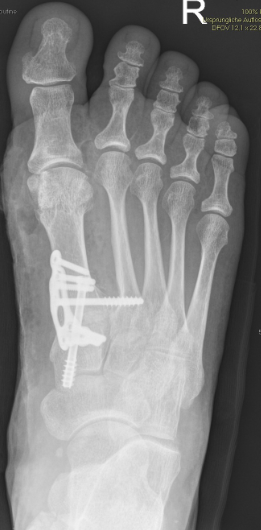

Gesamtes Spektrum der Fuß und Sprunggelenkchirurgie (Plattfuß, Spreizfuß, komplexe Vor-, Mittel- und Rückfußkorrektur, Krallenzehen und Hallux valgus/rigidus, Morton Neurinom)